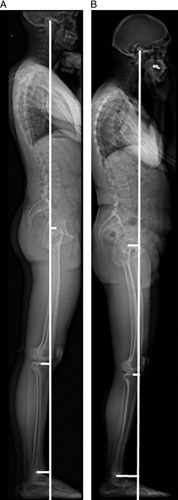

Sagittal alignment of a 26-year-old volunteer (A) and a 68-year-old volunteer (B). The figure is representative of the volunteer population as it shows a higher thoracic kyphosis in the older volunteer while maintaining the odontoid-knee distance by using compensatory mechanisms such as slight knee flexion and cervical extension.